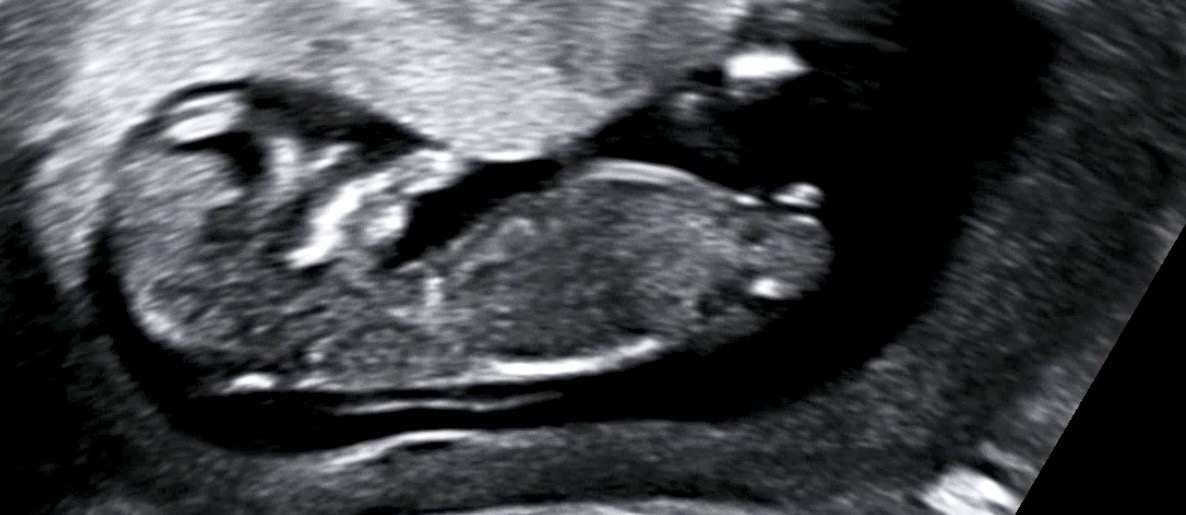

각도법 봐주실 천사맘님들 계실까요?

챗지피티, 빌리는 딸이라고하고 지인들은 아들같다하네요 어때보이실까요?